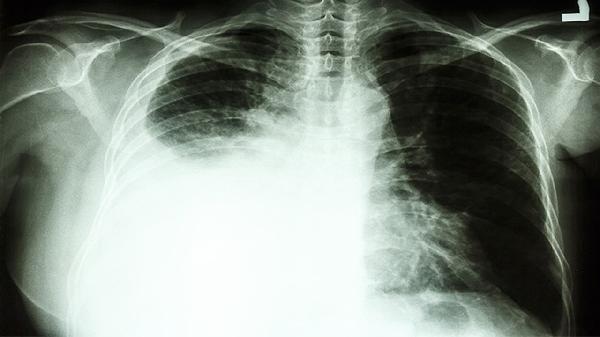

3、肺癌

消癌平片对肺癌有一定治疗作用。肺癌患者常见咳嗽、咯血、胸痛等症状,该药能抑制肺癌细胞扩散,减轻放化疗副作用。临床上多与吉非替尼片、卡铂注射液等药物联合使用,需严格遵循医嘱控制用药剂量。